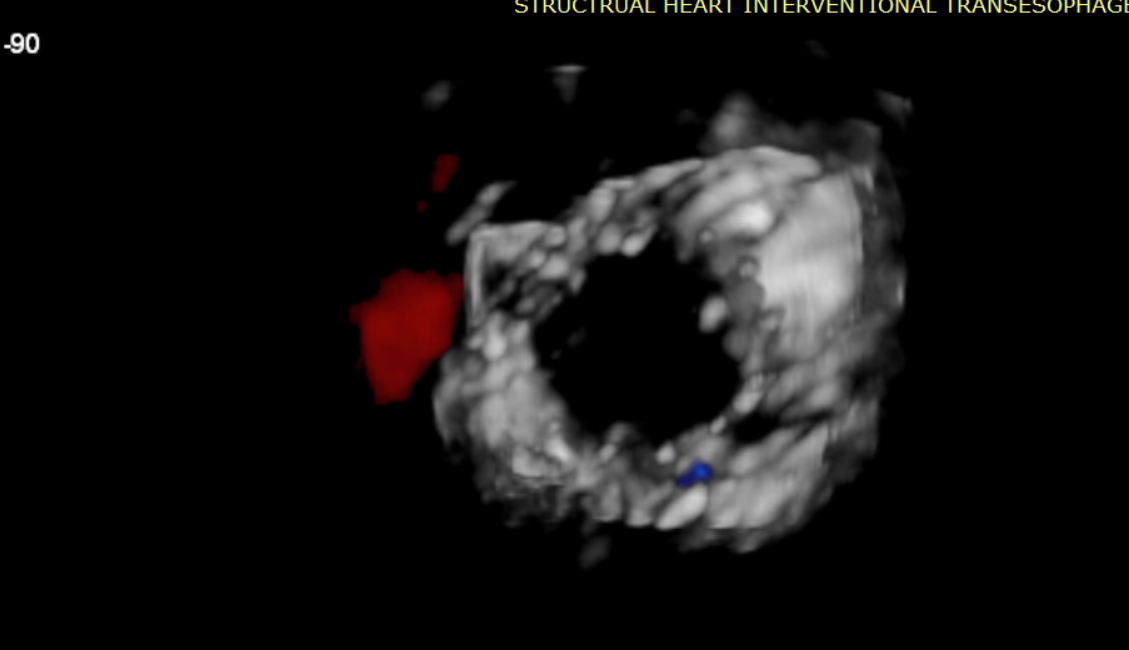

術(shù)前超聲提示大量三尖瓣反流